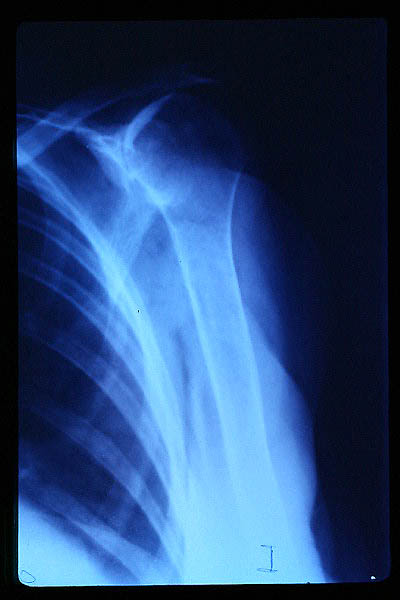

Fractura impactada de húmero .